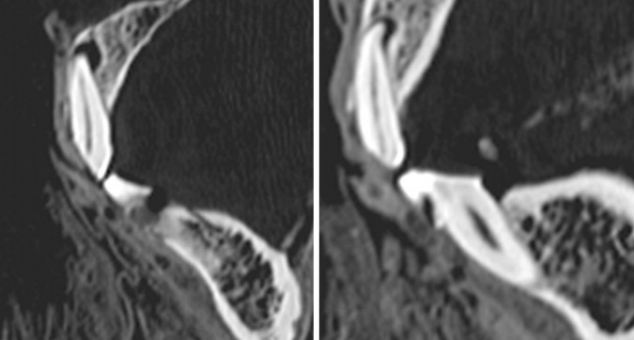

相比過(guò)去的研究器材,CT掃描儀使研究團(tuán)隊(duì)能夠更清晰詳盡地觀察填充物。

CT片顯示了木乃伊左邊第一顆門(mén)牙(左圖)和右邊第二顆門(mén)牙(右圖)的磨損狀況。